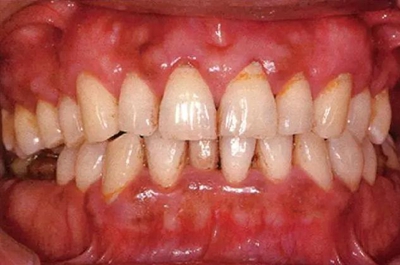

患有牙周病的牙周組織的臨床照片

44歲牙周炎女性的臨床照片

44歲患有糖尿病病史(未治愈)。菌斑控制不良。通過(guò)牙周探診,全頜有4~8mm的牙周袋,在X光片中可以看到上頜前牙處中度牙槽骨吸收,磨牙處重度牙槽骨吸收。二次齲齒和根面齲齒也有發(fā)生。可以看到浮腫性腫脹,收到刺激后會(huì)出血。